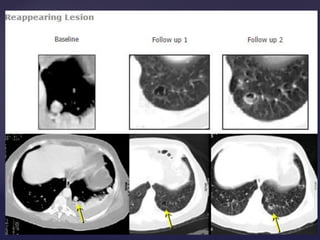

Lesión nueva = Progresión de la Enfermedad

LESIONES DE NUEVAS

Lesión nueva =Progresión de la Enfermedad LESIONES DE NUEVAS